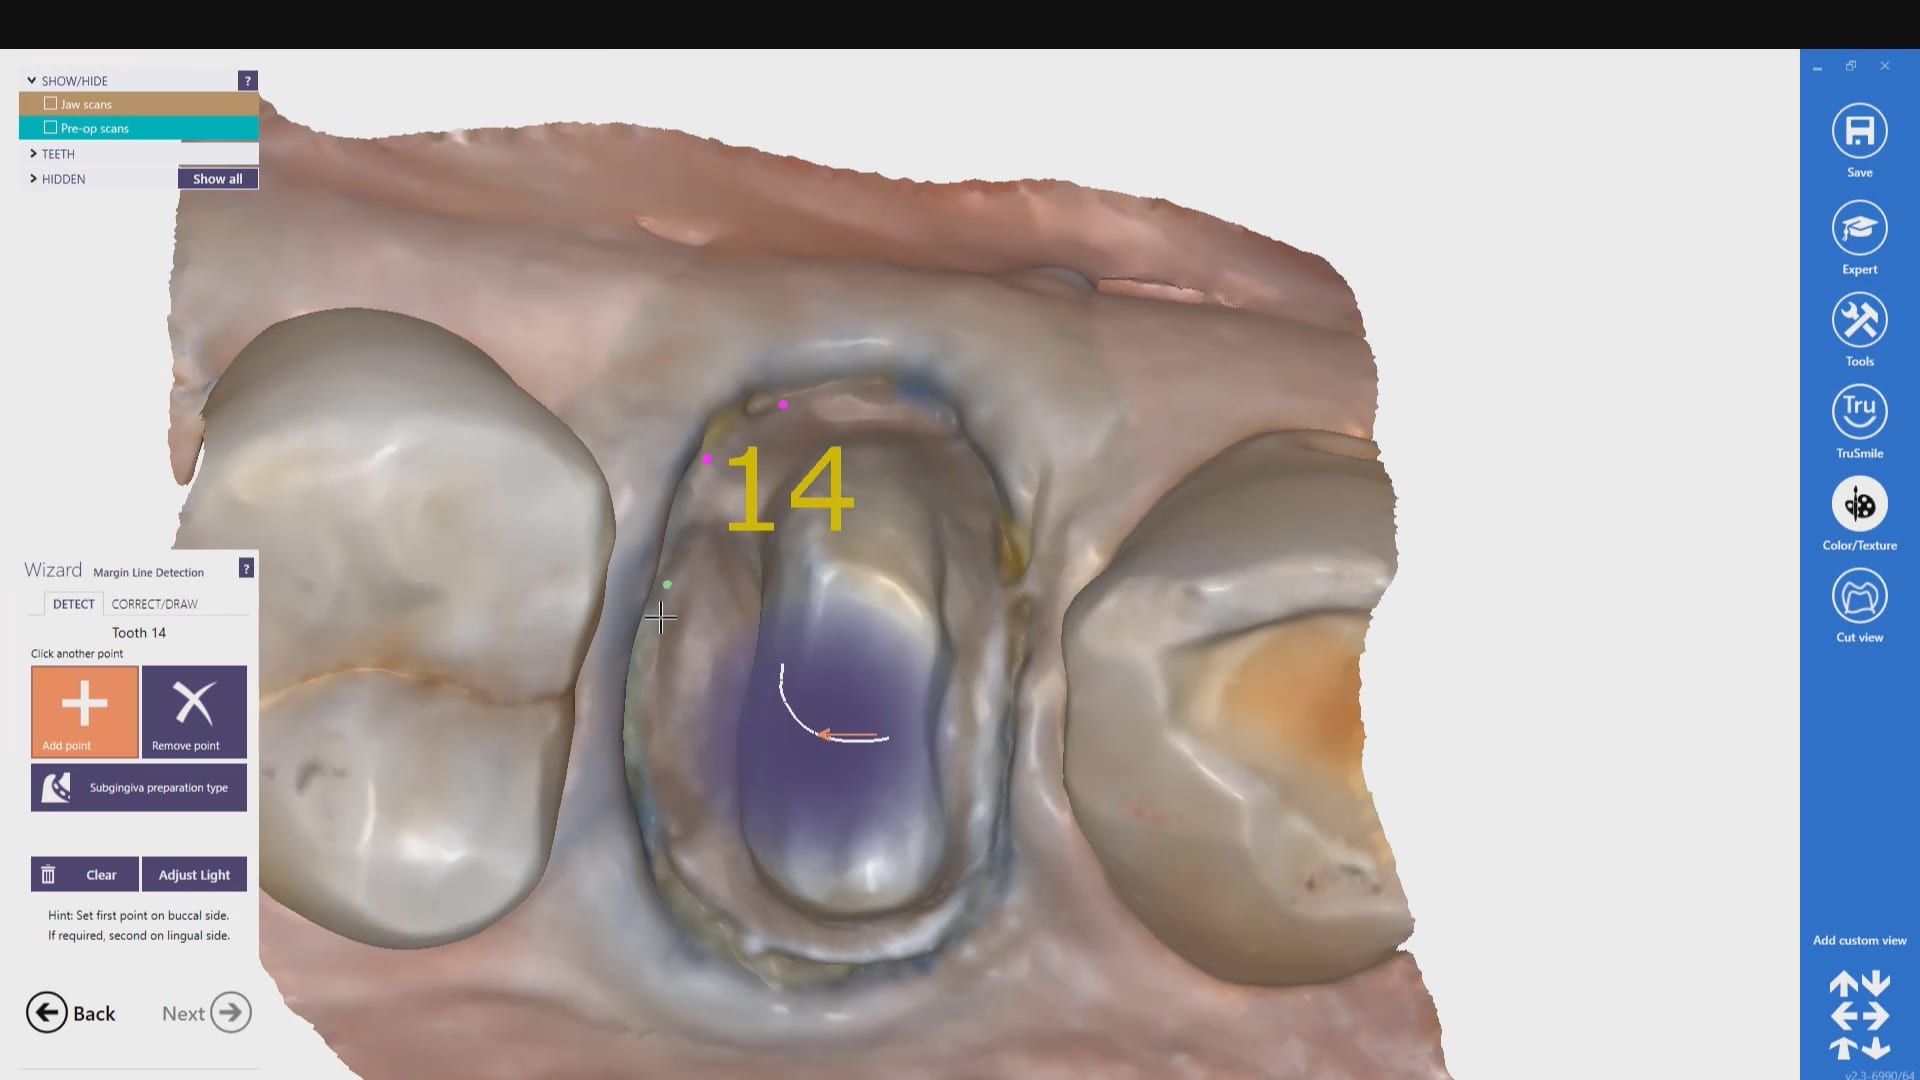

Case set up involved imaging the pre-existing condition in the pre-op catalog box. Excess information was cropped to reduce file size. The data was then copied to the maxillary arch catalog box and the area to prepared was edited out in preparation for final optical impressions.